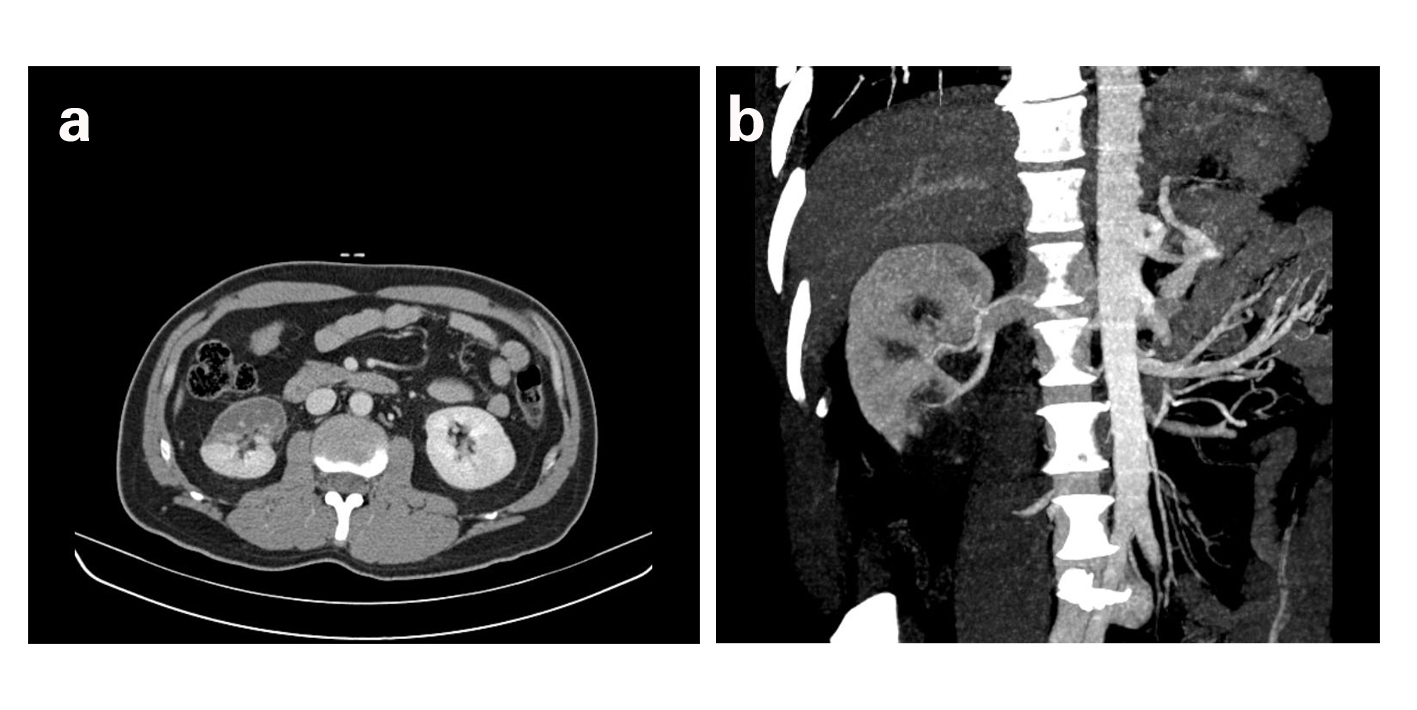

Male patient of 46 years old referred to the ER for prolonged right back pain, with 26 hours of evolution, with no history of trauma, fever or hematuria. Except for hypertension and hypercholesterolemia the patient had no other comorbidities such as coagulation disorders, diabetes mellitus, renal or heart disease. He denied smoking or alcohol habits. Blood analysis revealed leukocytosis (20.41 х 103/µL with 85.8% neutrophils), slight elevation of transaminases (aspartate transaminase 114 U/L, alanine transaminase 111 U/L) and frank elevation of lactate dehydrogenase (LDH) - 985 U/L (reference value 135 - 225 U/L). Urine dipstick was normal. Abdominal ultrasound revealed liver steatosis and a five millimeters polyp in gallbladder, with no renal, spleen or pancreas abnormalities. Contrast enhanced computed tomography (CECT) demonstrated partial renal infarction concerning the anterior and inferior portions of the right kidney due to occlusion of the inferior branch of the right renal artery (Fig 1a, b). According to vascular surgery observation, given the time course and infarct location, there was no indication for invasive procedures. The patient was admitted for surveillance and started low molecular weight heparin and intravenous antibiotics.

![]() Click for large image | Figure 1. a) Contrast-enhanced CT showing non-enhanced areas of the anterior surface and lower pole of the right kidney, suggestive of renal infarction. b) Coronal reconstruction demonstrating the absence of contrast enhancement of the inferior pole of the right kidney. |

CT angiography confirmed the existence of occlusion of the lower branch of the anterior division of the renal artery with subsequent infarction of the inferior pole of the right kidney. The renal angiogram revealed multifocal infarction, absence of significant stenosis of the right renal artery and probable vascular malformation in a branch of the renal artery that, at the time, wouldn’t justify intervention or the clinic presentation. The patient was discharged 7 days later on oral anticoagulation in therapeutic range (INR between two and three) and surveillance in Urology and Vascular Surgery consultation. The follow-up renal scintigraphy with Tc-99m-DMSA performed two months later revealed atrophy of the right kidney, with reduced uptake of the drug and 38% of differential renal function for the right kidney and 62% for the left kidney. Re-evaluation with renal angiography in Vascular Surgery consultation revealed a saccular aneurysm of the right renal artery, most likely to be the primary cause of renal infarction. At 6 months follow-up the patient presented normal renal function and no relevant symptoms.